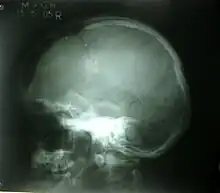

Depressed fracture

Depressed skull fracture.

A depressed skull fracture is a type of fracture usually resulting from blunt force trauma, such as getting struck with a hammer, rock or getting kicked in the head. These types of fractures—which occur in 11% of severe head injuries—are comminuted fractures in which broken bones displace inward. Depressed skull fractures present a high risk of increased pressure on the brain, or a hemorrhage to the brain that crushes the delicate tissue.

Compound depressed skull fractures occur when there is a laceration over the fracture, putting the internal cranial cavity in contact with the outside environment, increasing the risk of contamination and infection. In complex depressed fractures, the dura mater is torn. Depressed skull fractures may require surgery to lift the bones off the brain if they are pressing on it by making burr holes on the adjacent normal skull.[2]